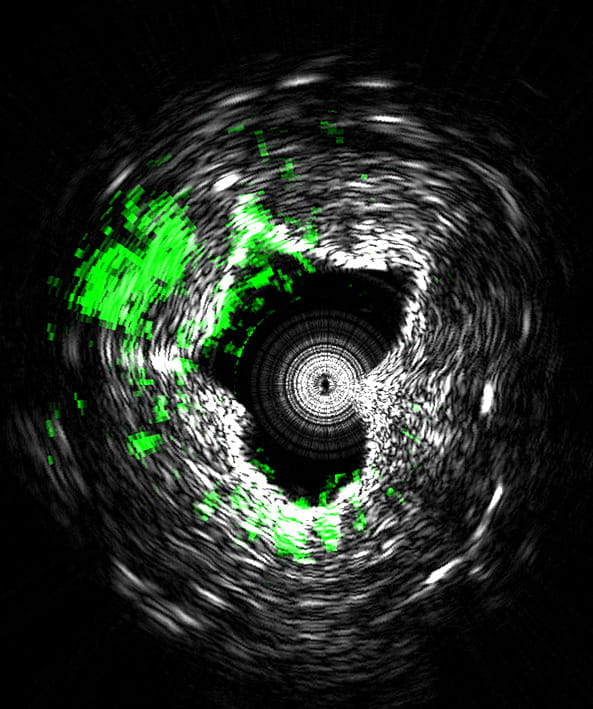

The system takes precise three-dimensional images of plaques lining arteries and identifies deposits that are likely to rupture and cause heart attacks, said Ji-Xin Cheng, Ph.D., a professor in Purdue University’s Weldon School of Biomedical Engineering and Department of Chemistry.

The imaging reveals the presence of carbon-hydrogen bonds making up lipid molecules in arterial plaques that cause heart disease. Research findings are detailed in a paper appearing online Tuesday (Nov. 4) in the Nature journal Scientific Reports.

Research in the area has been hindered by the inability to perform high-speed imaging in tissue. The researchers solved the problem by developing a Raman laser using a laser that produces 2,000 pulses per second, each pulse capable of generating an image, representing a 100-fold increase in the imaging speed of the new technology, called intravascular photoacoustic imaging.